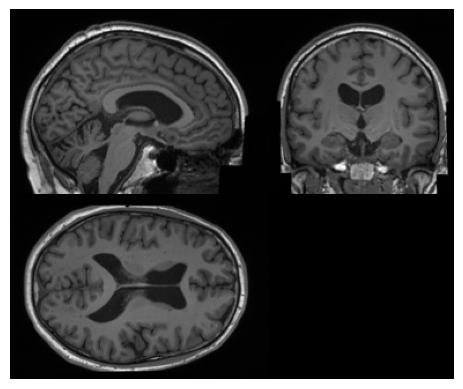

Figure 1 - Synthetic image from the model.

This model is trained using the Latent Diffusion Model architecture [1] and is used for the synthesis of conditioned 3D brain MRI data. The model is divided into two parts: an autoencoder with a KL-regularisation model that compresses data into a latent space and a diffusion model that learns to generate conditioned synthetic latent representations. This model is conditioned on age, sex, the volume of ventricular cerebrospinal fluid, and brain volume normalised for head size.